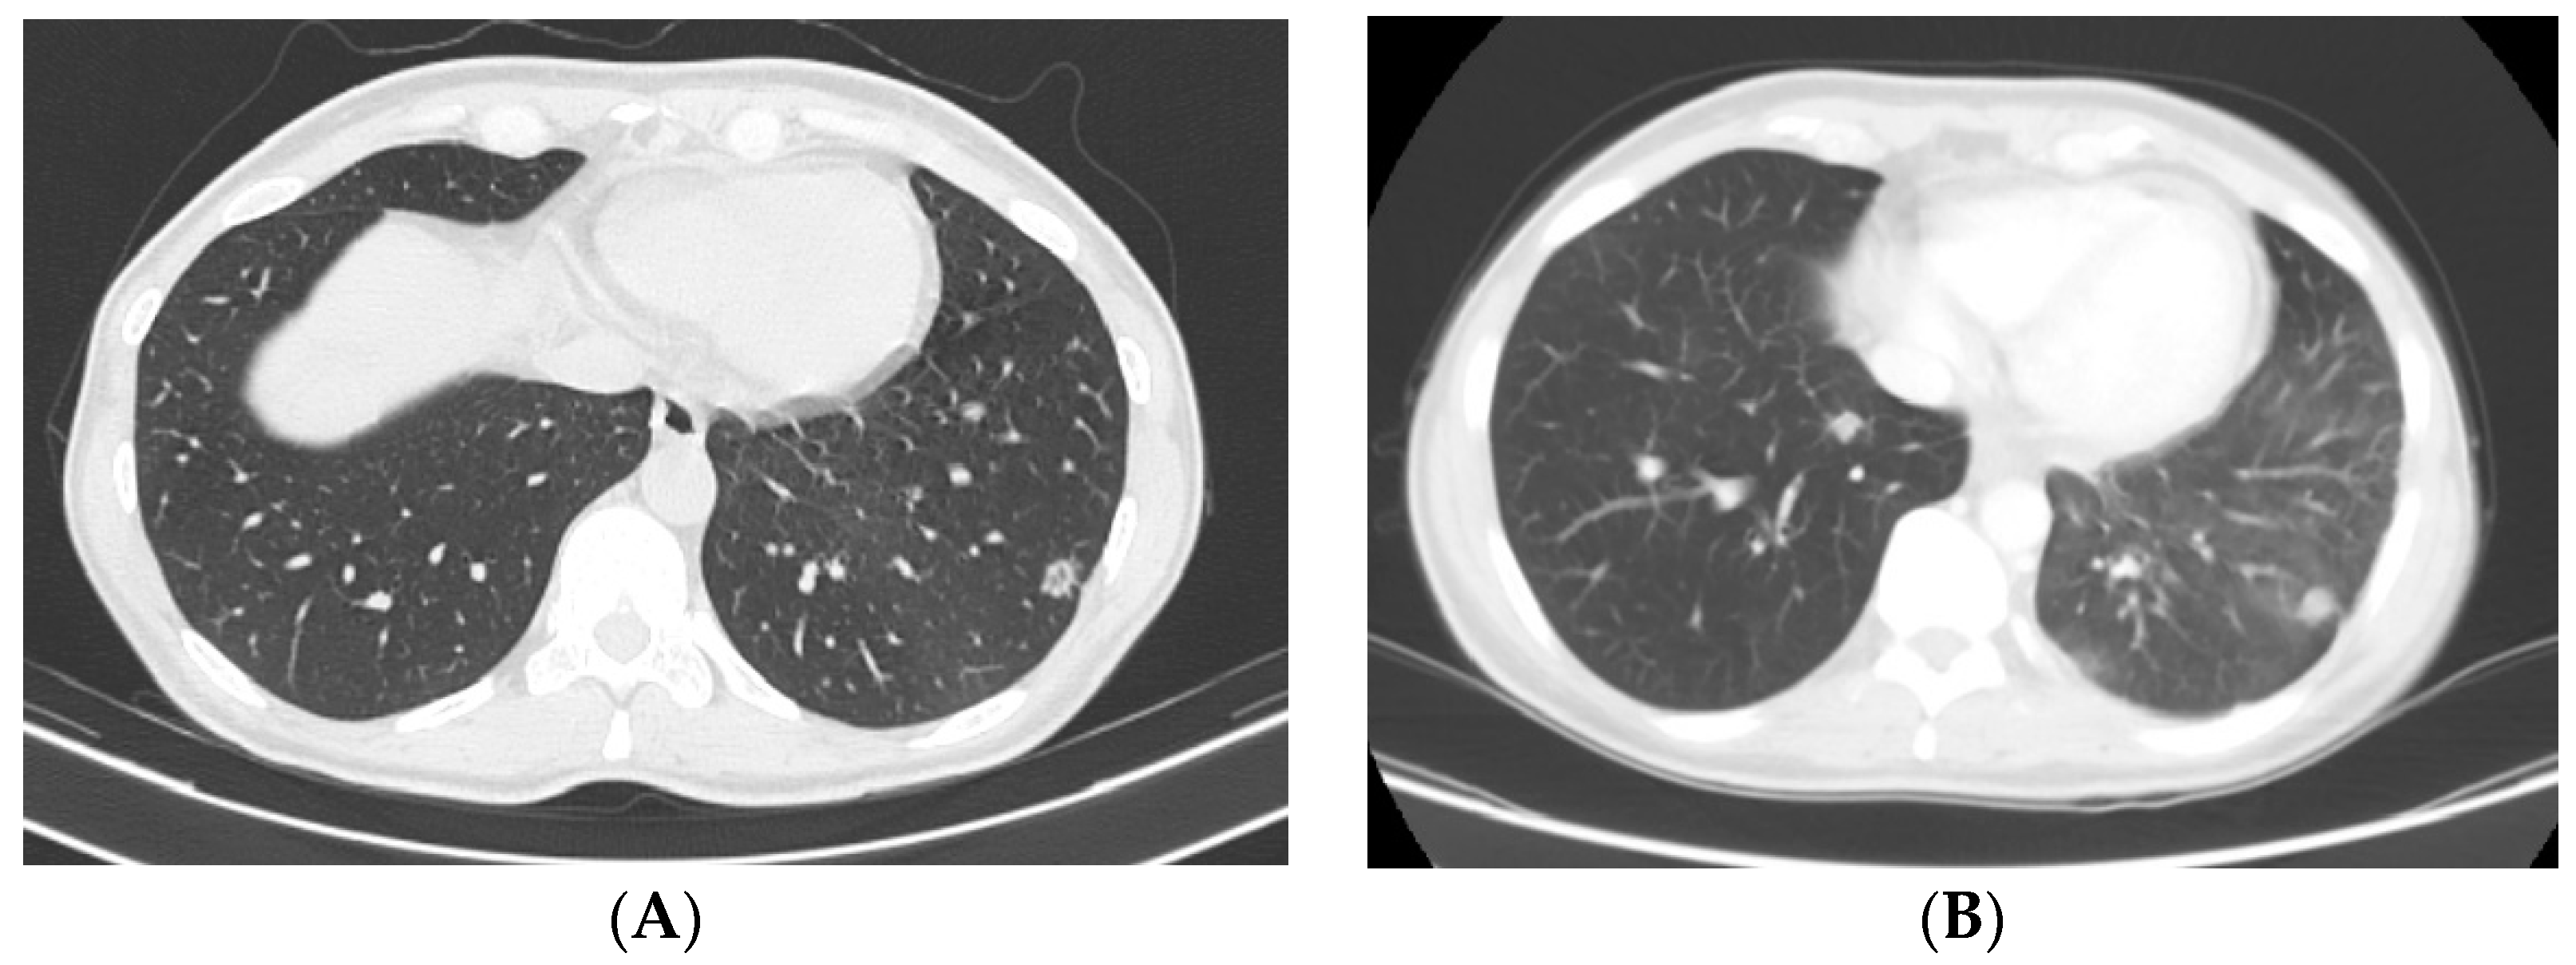

Clinical Scenario

- Vaidya, P.; Mehta, A.; Ragab, O.; Lin, S.; In, G.K. Concurrent radiation therapy with programmed cell death protein 1 inhibition leads to a complete response in advanced cutaneous squamous cell carcinoma. JAAD Case Rep. 2019, 5, 763–766. [Google Scholar] [CrossRef]